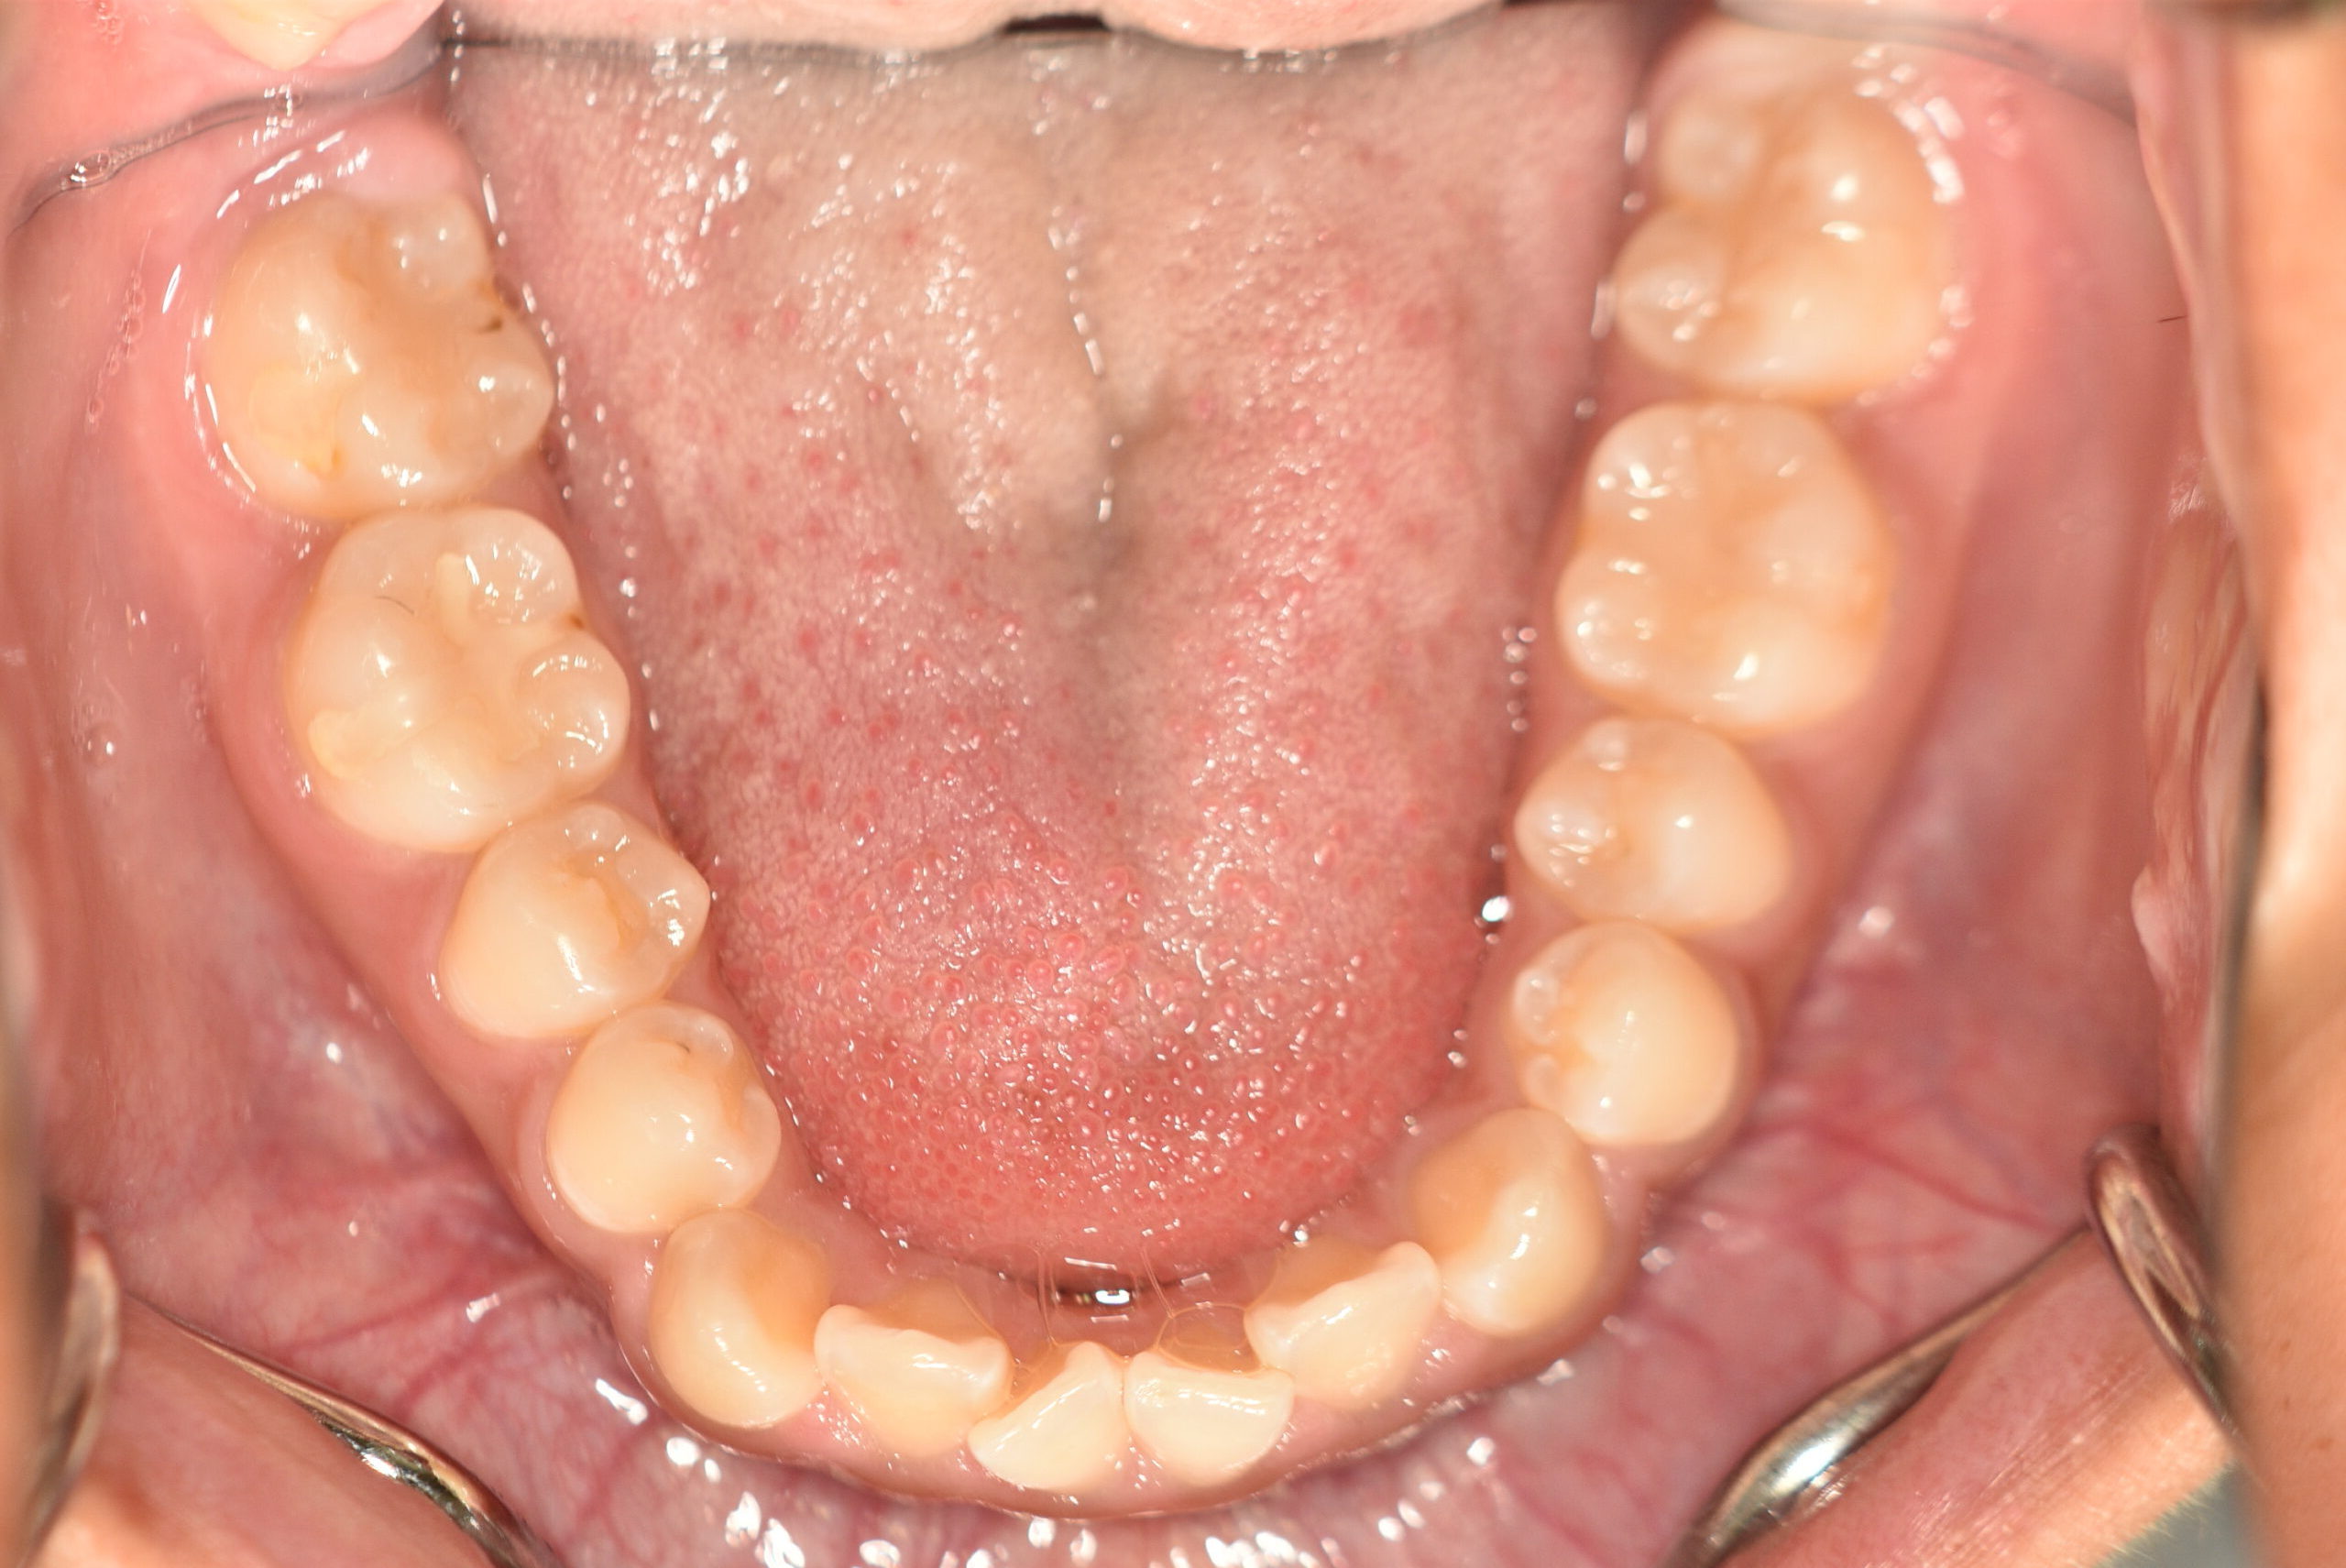

| 治療内容の詳細 | 初診時14歳の女性で、歯のがたつき、かみ合わせを気にされ来院されました。 検査の結果、上下顎前歯部叢生および開咬を伴うアングルⅠ級不正咬合と診断しました。 治療としては、非抜歯の上、セルフライゲーションブラケット装置(デーモンシステム)と マウスピース矯正装置(インビザライン)で配列を行いました。 開咬については、顎間ゴムの協力もあり改善されました。 治療期間は、2年2ヶ月でした。 |